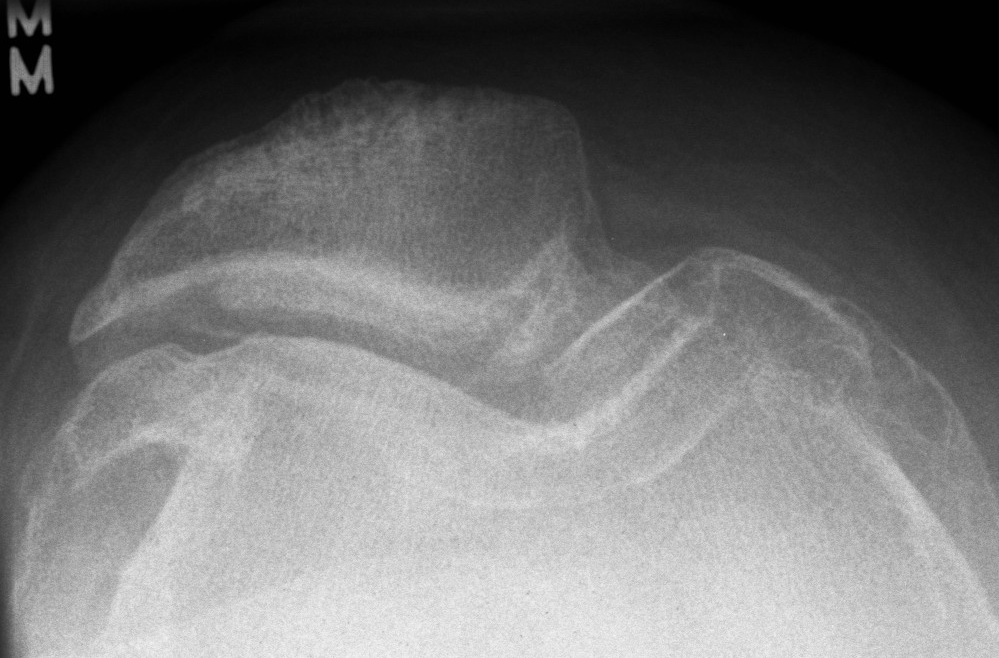

X-ray

Narrowing / osteophytes / sclerosis

Tilt / subluxation

Tilt Subluxation / osteophytes

Severe lateral PFJ OA in the setting of maltracking / subluxation / tilt